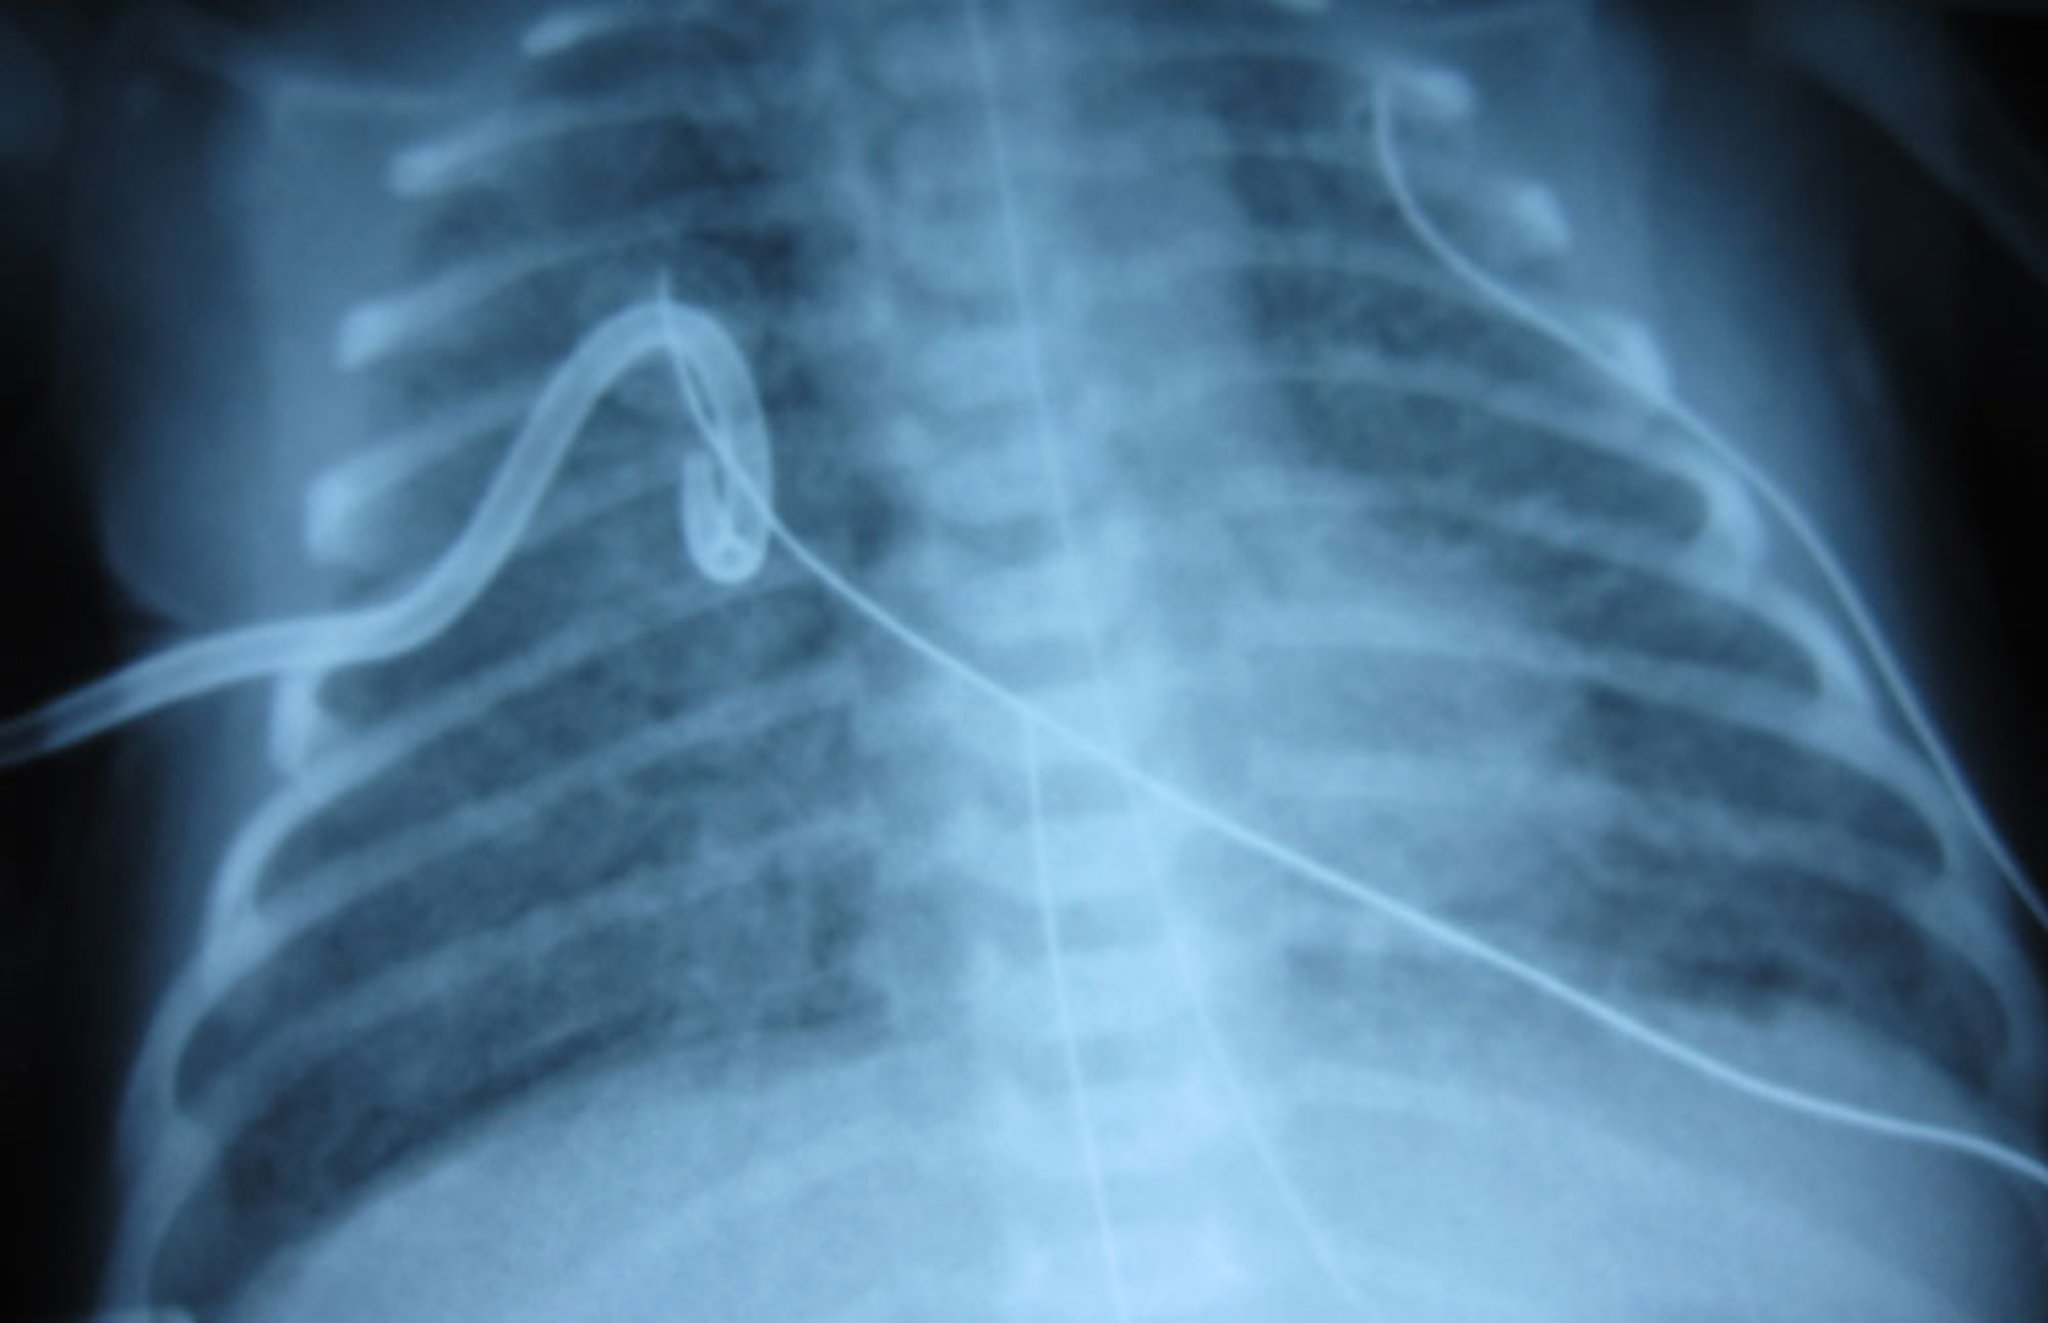

Pneumothorax After Chest Tube Placement

After placement of a pigtail chest tube, the right lung in this image has re-expanded, with lung markings clearly visible.

The pulmonary edema is due to congenital heart disease (total anomalous pulmonary venous return) and is not directly related to the pneumothorax.

Image courtesy of Arcangela Balest, MD.